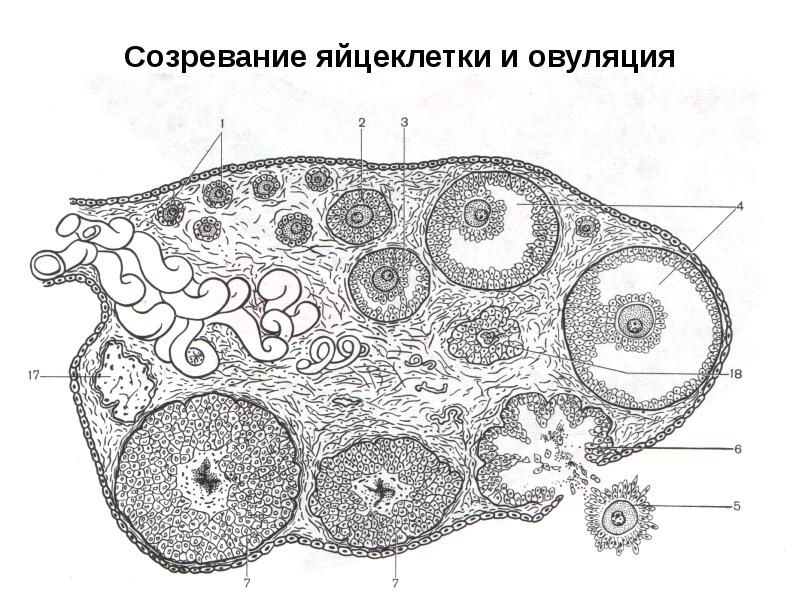

Созревание фолликула в яичнике: этапы и процессы

Раздел: Другие животные